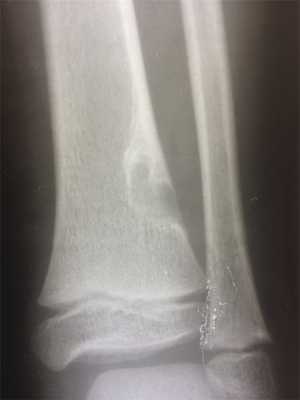

(Слева) Рентгенография в ПЗ проекции: умеренно агрессивный, вспученный литический диафизарный очаг с псевдотрабекуляцией и патологическим переломом в дистальном отделе. Данные признаки не специфичны. Двумя наиболее вероятными диагнозами являются неоссифицирующая фиброма и десмопластическая фиброма.

(Справа) МРТ, аксиальная проекция, режим Т1: внутрикостный очаг у этого же пациента В, характеризующийся сигналом, интенсивность которого немногим ниже сопряженной мышцы. Визуализируется выраженная вспученность малоберцовой кости. Такие признаки неспецифичны, однако сигнал очень низкой интенсивности предполагает наличие фиброзного очага.